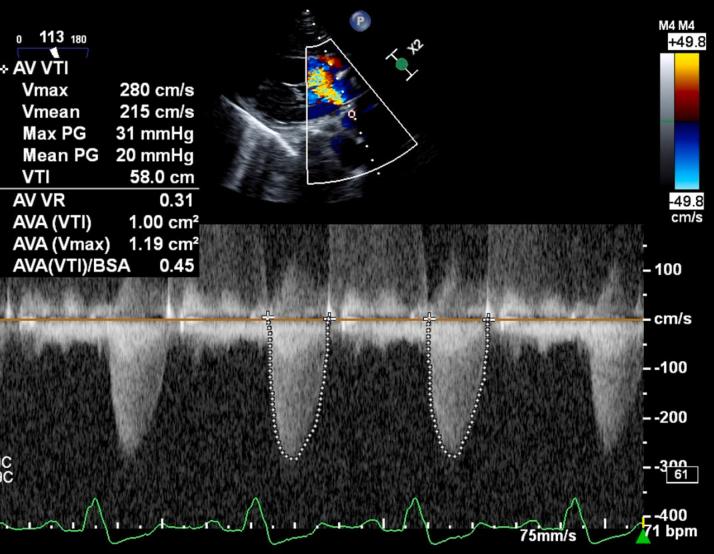

A 59-year-old man with a history of total body radiation presented with fatigue and dyspnea. Multimodality imaging, including echocardiography, cardiac magnetic resonance, and invasive hemodynamic assessment, confirmed severe aortic stenosis and mild constrictive physiology. Because of an elevated surgical risk and minimum contribution of constrictive physiology to symptoms, the multidisciplinary team opted for transcatheter aortic valve replacement over surgical aortic valve replacement with pericardiectomy.

一名有全身放疗史的59岁男性出现疲劳和呼吸困难。包括超声心动图、心脏磁共振和有创血流动力学评估在内的多模态成像证实存在严重主动脉瓣狭窄和轻度缩窄性生理改变。由于手术风险升高且缩窄性生理改变对症状的影响最小,多学科团队选择经导管主动脉瓣置换术而非行心包切除术的外科主动脉瓣置换术。